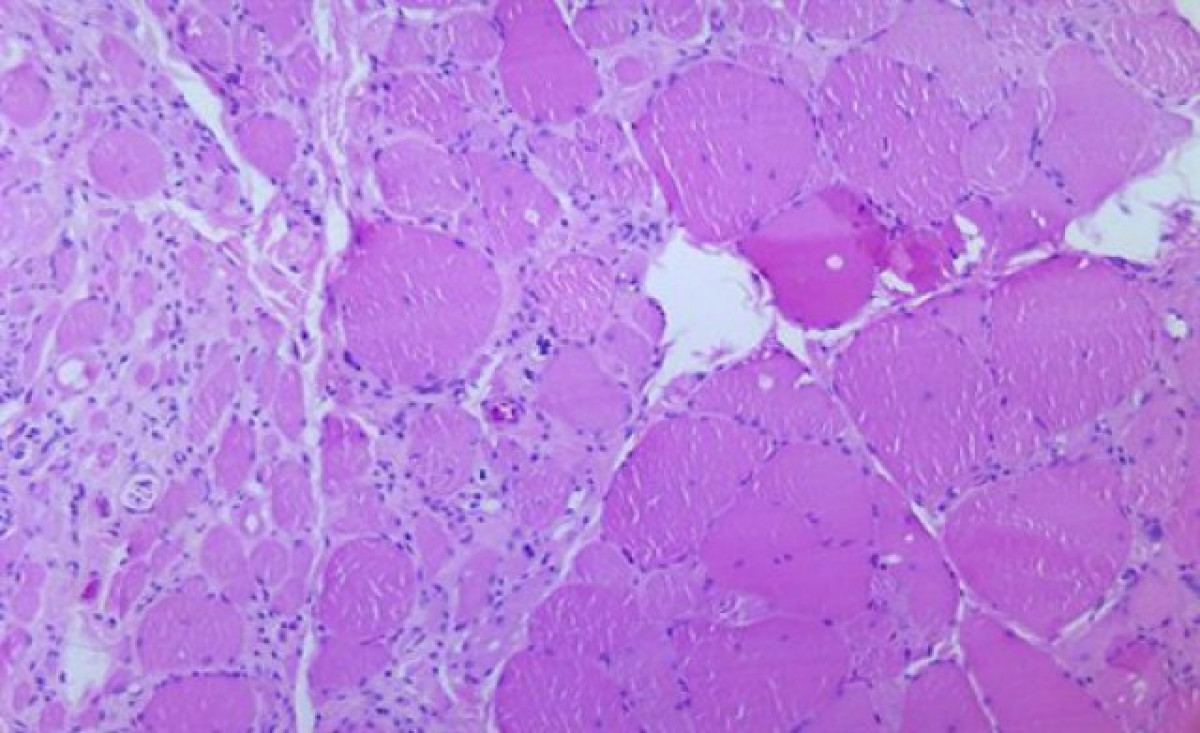

La poliomielitis és una malaltia infecciosa causada per un enterovirus del qual hi ha tres serotips (PV1, PV2 i PV3). El més habitual és el tipus 1, mentre el 3 ha estat eradicat a tot el món, segons ha anunciat aquest dijous un comitè independent d'experts. El PV1 es troba molt localitzat en algunes regions del Pakistan (76 casos el 2019) i l'Afganistan (16 casos el 2019). El serotip tipus 2 està eradicat des de setembre de 2015, després que transcorreguessin més de 15 anys des de l'últim cas a Uttar Pradesh (Índia).